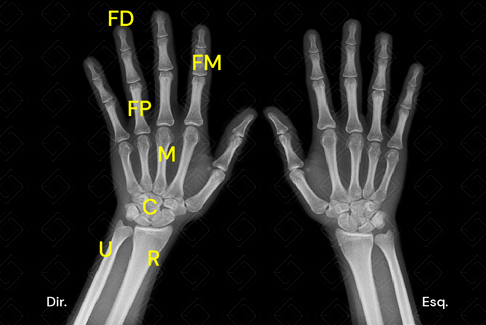

Texto alternativo para a imagem Radiografia de mãos e punhos para avaliação de idade óssea. Créditos: Athena Hub/Medical Harbour

Legenda: C: ossos do carpo; FD: falanges distais; FM: falanges médias; FP: falanges proximais; M: metatarsos; [cms-watermark] [cms-watermark] [cms-watermark] [cms-watermark] [cms-watermark] R: rádio; U: ulna.